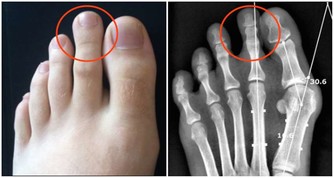

骨質疏鬆即骨質疏鬆症,是多種原因引起的一組骨病,骨組織有正常的鈣化,鈣鹽與基質呈正常比例,以單位體積內骨組織量減少為特點的代謝性骨病變。在日常的生活中,我們最常見的骨質疏鬆的症狀就是骨頭疼痛,身長縮短、駝背,容易骨折,還有就是呼吸功能下降。

2、香菜:醫學研究表明,人過40歲後,骨生成減少,骨皮質變薄,尤以婦女為甚。此時,女性的骨頭猶如雞蛋,骨皮質薄似蛋殼,脆弱易碎。專家提醒,進入中年期的婦女應多吃含硼食物,以利身體吸收礦物質,保護骨骼,而香菜中的含硼量就很高。